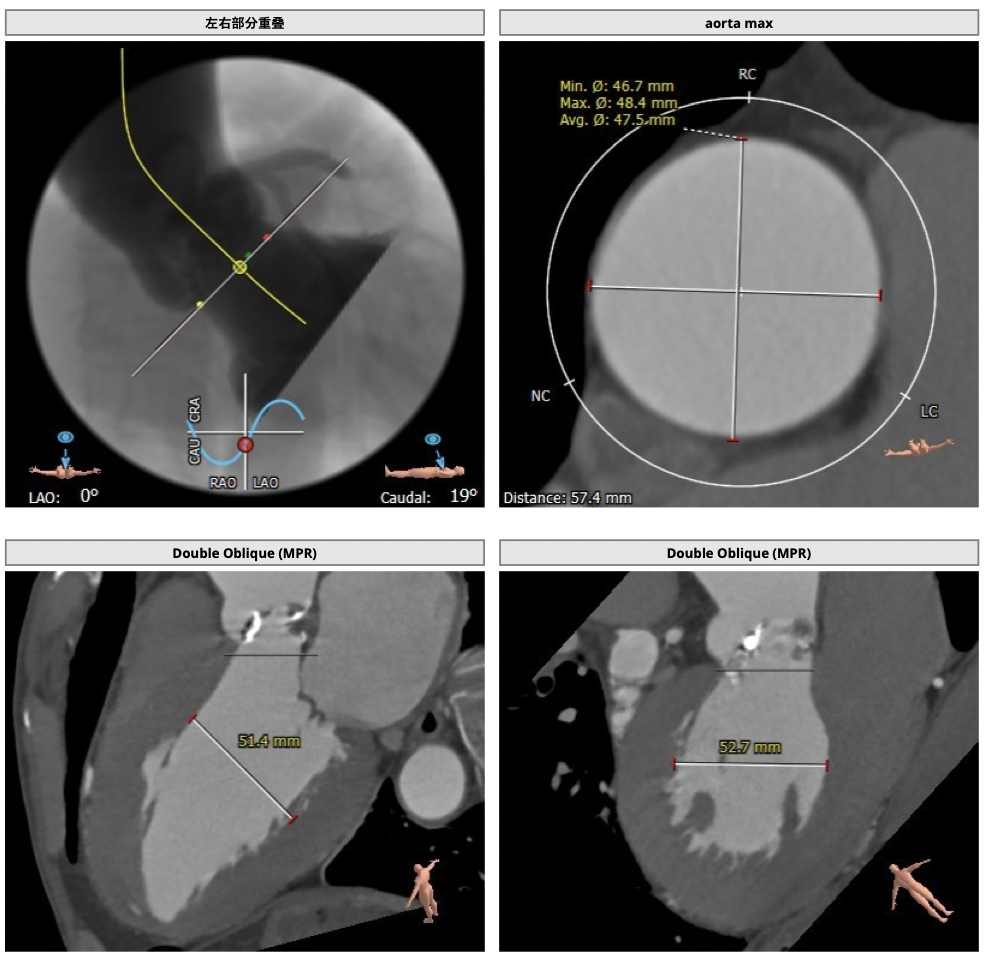

主动脉CT

图片

CT分析:

*患者为TYPE1型二叶瓣,左右钙化融合,冠脉高度高,法式窦结构可,心脏角度约50°,左室大小可,心肌增厚,升主动脉未见明显增宽。主动脉弓部走形较平缓,右侧股动脉可作为主入路。

经分析研判,拟从右侧股动脉穿刺入路,使用23mm球囊预扩,选用L29号的VenusA-Valve瓣膜,采用VenusA-Plus可回收输送系统进一步确保手术安全,瓣膜释放后结合造影和超声情况,决定是否后扩。